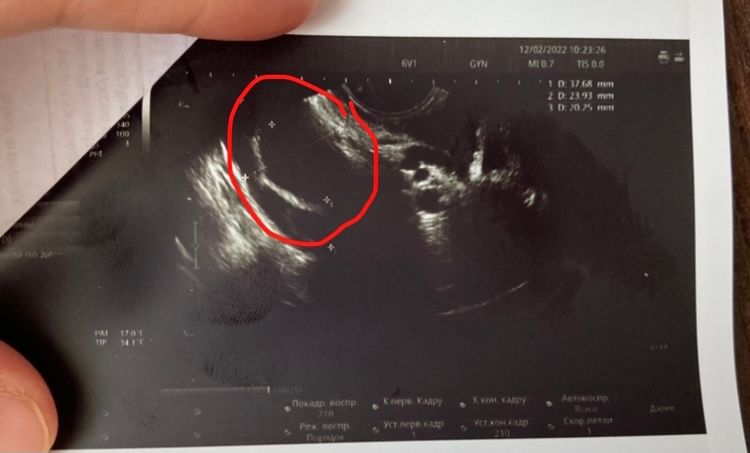

Девушки.У меня такой вопрос Может ли узист перепутать Доминантный фолликул с Желтой телой?

просто когда была на 17 День цикла Сказали вот вот овуляция будет у меня .Потом сегодня уже 25 день цикла пошла посмотреть есть ли Жт ,а узистка говорит Дф 2 см . 🙄разве может на 25 день цикла только быть овуляция?Месячные должны уже 17 придти .или все таки

вот вот овуляция будет?эндик 10 мм

Всё может быть, поздняя овуляция, фото у вас очень плохо видно